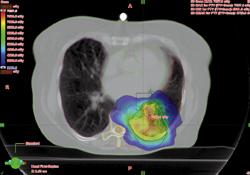

Doctors at the VU Medical Center in Amsterdam have been pioneering RapidArc treatments for lung tumors. Their stereotactic treatments for early stage lung tumors, details of which have been published in Radiotherapy and Oncology, began last year.

“The average delivery time using our standard non-coplanar beams was previously around 15 minutes for these complex cases, but nearly a third of patients required an additional set-up procedure during delivery as a consequence of intra-fraction shift,” said Suresh Senan, Ph.D., professor of clinical experimental radiotherapy. “With RapidArc we have reduced delivery times to between 4.5 and 11 minutes, depending on the risk-adapted fractionation scheme used. We hope to reduce treatment times further to less than six minutes for all cases by the end of this year.”

“We are also pleased with the highly conformal plans achieved with RapidArc, which allows us to further reduce doses to critical structures like the chest wall, especially for non-spherical tumors,” he said. “Even larger tumors are now being treated and our patients appreciate the ability to complete their sessions quickly.”

Ben Slotman, M.D., Ph.D., chairman of the hospital’s department of radiation oncology, added, “We have reported excellent results with lung stereotactic radiotherapy previously, but RapidArc has now allowed for improvements in departmental efficiency and cone-beam CT-guided setup on the tumor ensures that we are treating the tumors accurately.”